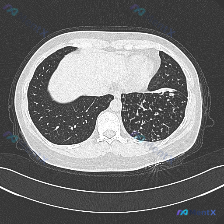

看到一个典型的胸部CT影像病例,整理了一下资料和分析思路,和大家分享讨论。 基本影像信息 这是一张清晰度良好的胸部CT横断面肺窗图像,扫描层面位于主动脉弓上缘至气管分叉上方水平,窗位窗宽适合观察肺实质,无明显运动伪影。 影像核心表现 1. 肺实质病变:双肺均见异常密度影,右肺上叶受累更明显,表现为多...